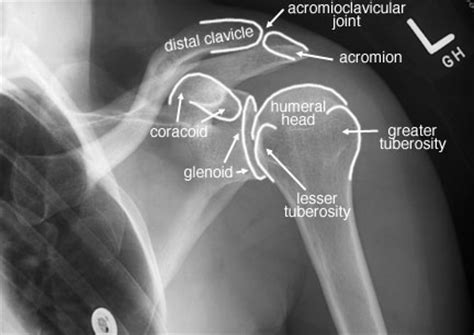

Radiographic Anatomy Of The Skeleton: Shoulder -- Internal Rotation

anatomy shoulder ray rotation internal normal labelled skeleton radiographic radiology xray ap hombro uwmsk human medical bones anatomia anatomÃa radiography